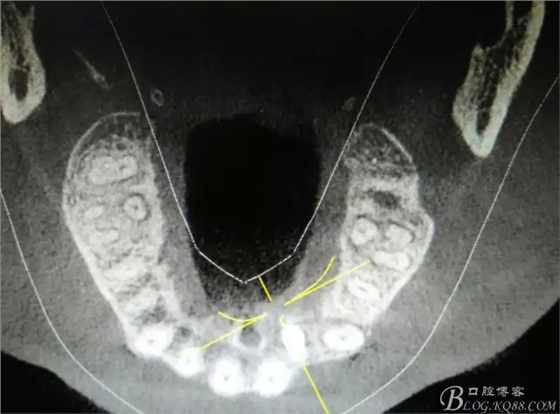

圖2.CBCT的三維成像及縱剖面、水平面影像